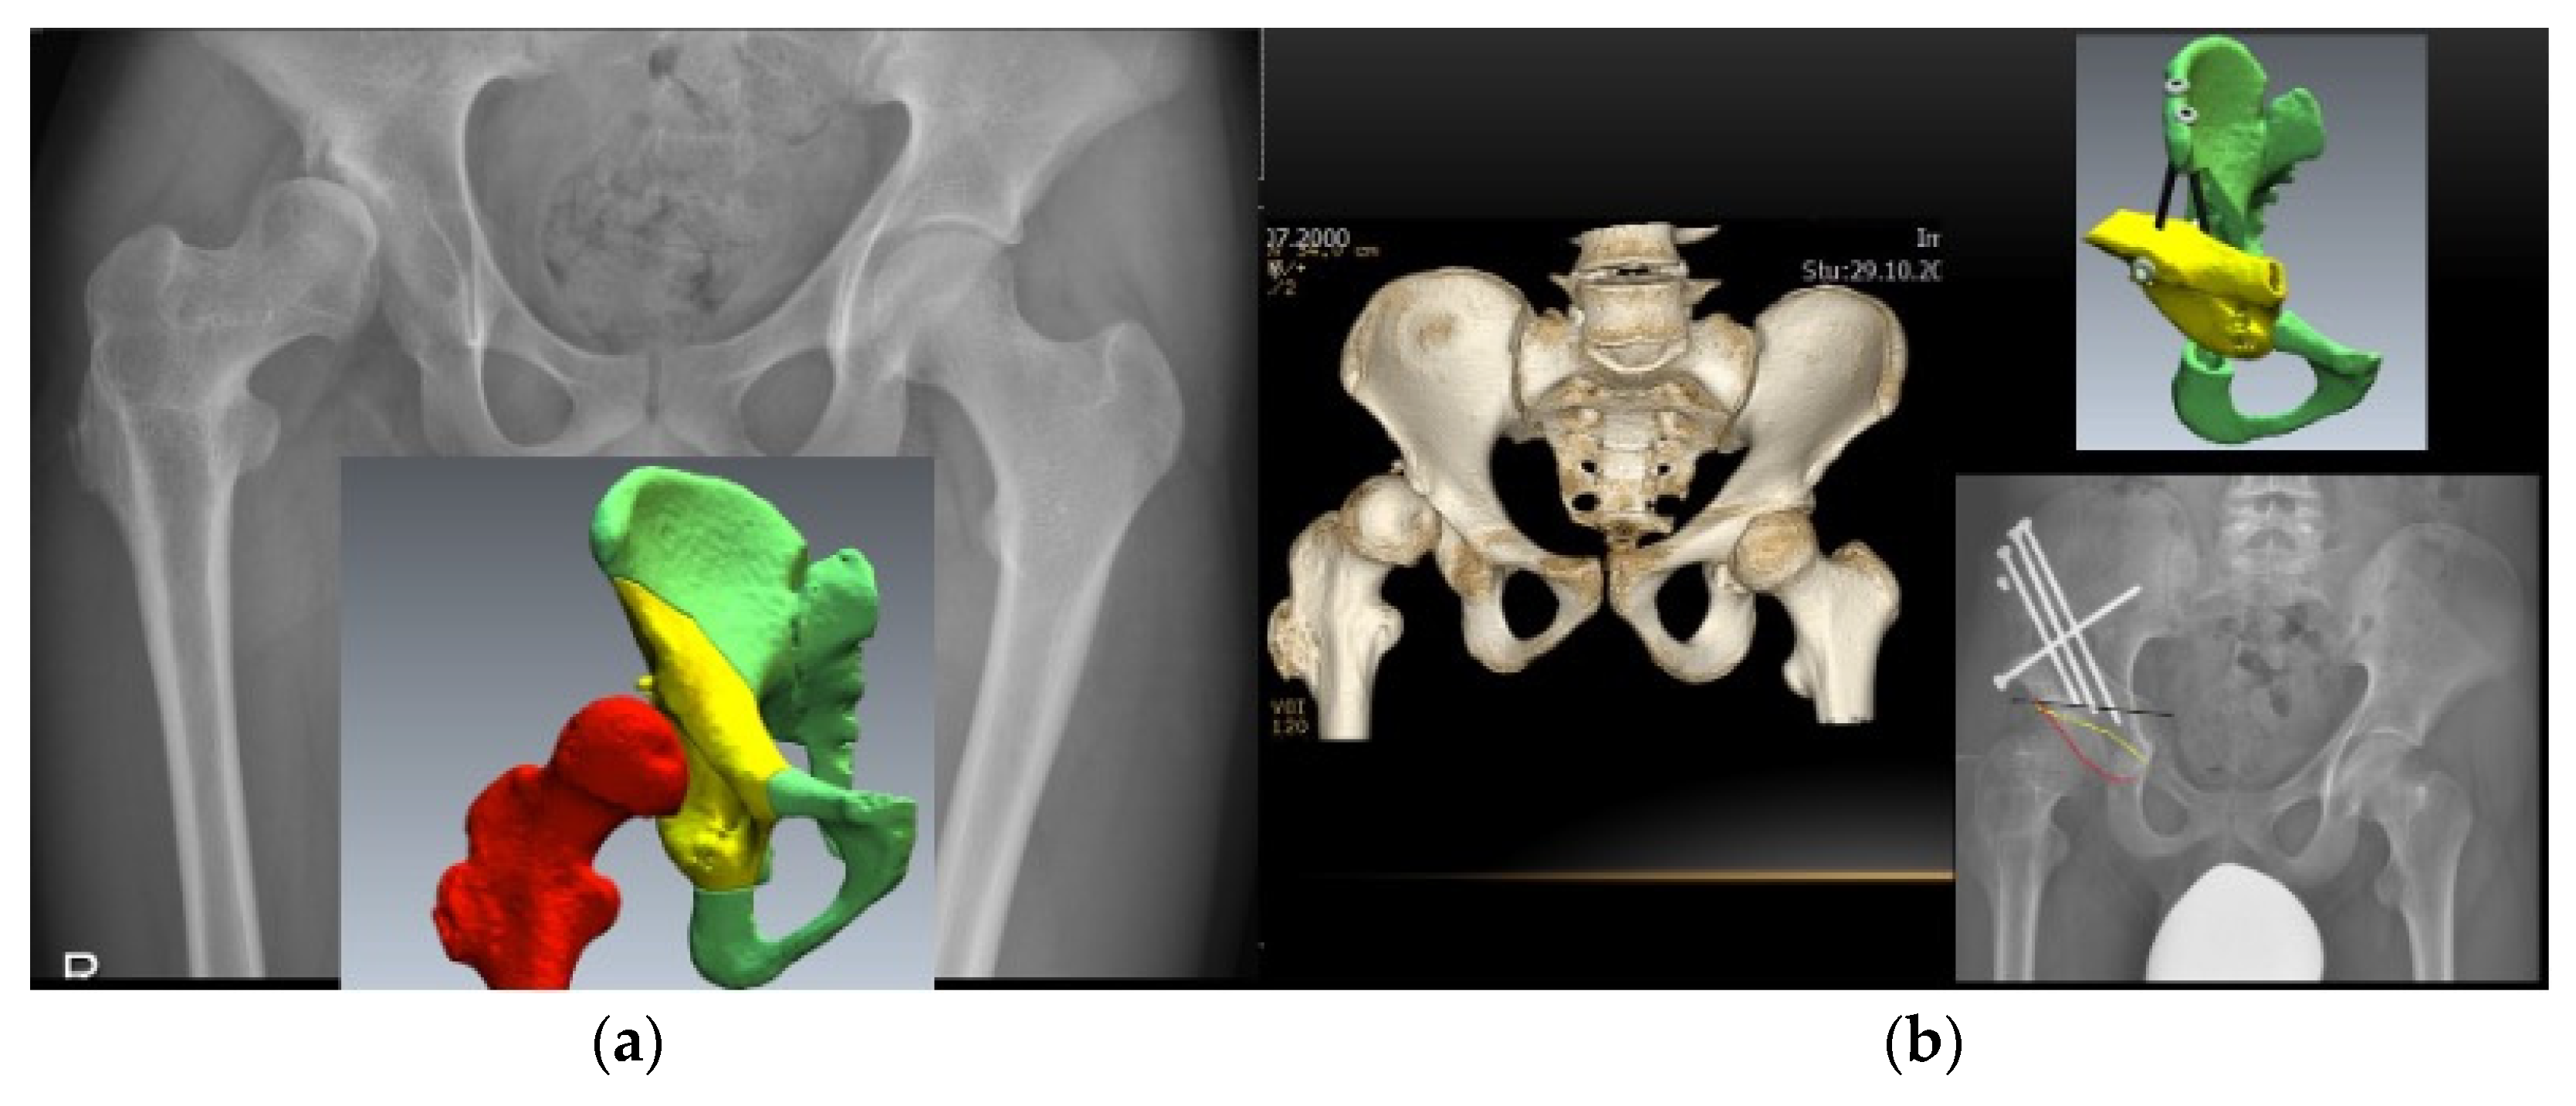

6. Computer-Assisted Orthopaedic Surgery

- Brumat, P.; Mihalič, R.; Benulič, Č.; Kristan, A.; Trebše, R. Patient-Specific Template and Electromagnetic Navigation Assisted Bilateral Periacetabular Osteotomy for Staged Correction of Bilateral Injury-Induced Hip Dysplasia: A Case Report. J. Hip Preserv. Surg. 2021, 8, 192–196. [Google Scholar] [CrossRef] [PubMed]